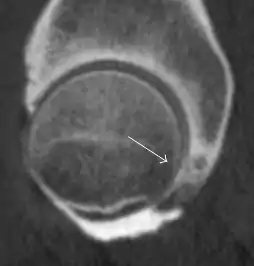

MRI has been shown to have 100% sensitivity and specificity in prospective studies of occult hip fractures. These fractures were diagnosed by bone marrow edema and a low signal fracture line, mainly on T1 or T2 weighted images (Figure 10).[1]

Figure 10:

Stress femoral neck fracture in a young athlete barely visible in X-ray film as a sclerotic line (arrow)[1]

In this case, Tc 99 scintigraphy shows a band of uptake[1]

Furthermore, T1 (left) and DP fat saturated (right) weighted MR images showed the fracture line and a pattern of edema.[1]